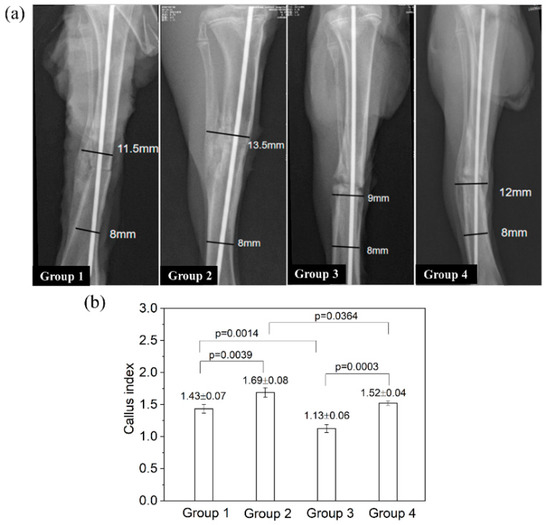

On postmortem radiographs (Figure 8a), Group 1 (blank control) showed a clear periosteal reaction (see the left side of the tibia) and extensive callus formation bridging the fracture ends. Group 2 had a weakly visible fracture line and satisfactory cortex continuity, suggesting a faster union (vs. Group 1). In comparison, Group 3 displayed a wide fracture gap with signs of bone resorption at the fracture ends, showing a delayed union. Group 4 had a narrower fracture line (vs. Group 3) and extensive callus bridging the gap, indicating a status of healing superior to Group C but inferior to Group B. The callus index of Group 3 was significantly lower than that of all other groups (all p < 0.01; Figure 8b). The callus index of Group 2 was significantly higher than that of Group 1 (p = 0.0039); the callus index of Group 4 was slightly higher than that of Group 1, but the difference was not statistically significant (p = 0.377).

Figure 8.

The radiographic examinations of rat tibia after implant removal on day 28. (a) The representative images of the callus formation in different groups. Lines and numbers indicate how the callus index was determined. (b) The value of callus index for different groups.